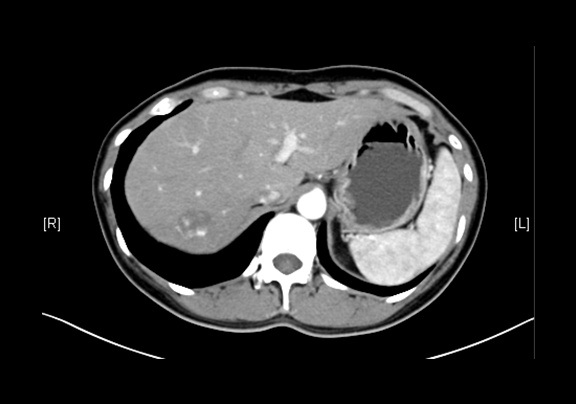

上腹部增强CT示:肝右叶海绵状血管瘤可能性大;肝囊肿;左肾上极肿瘤可能性大;双肾多发囊肿。

术前CT检查:

平衡期